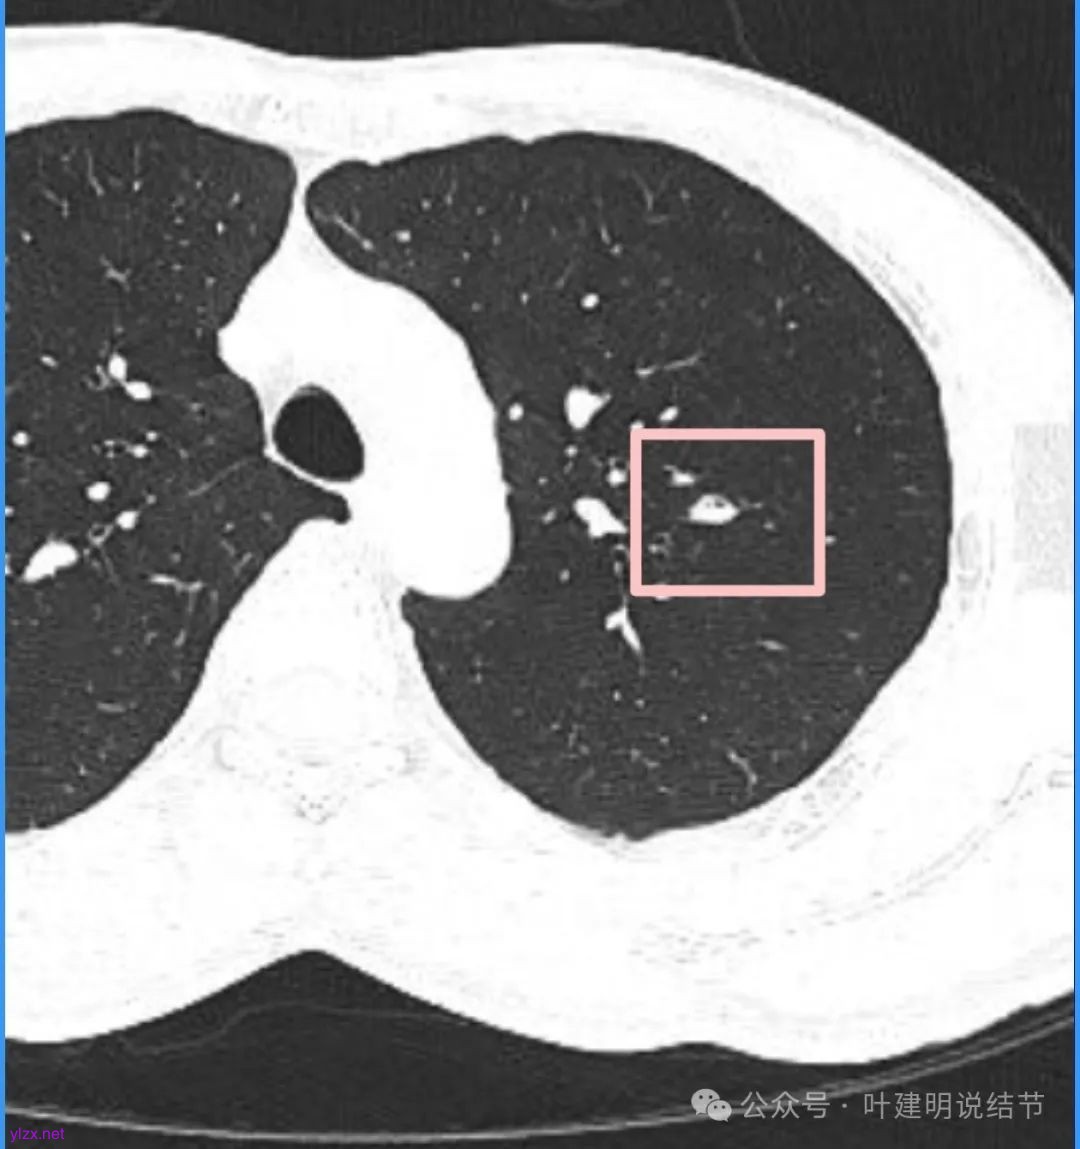

再看看近半年前2024年11月时的影像:

我们发现一是病灶与25年3月的几乎没有区别,二是原来蓝色箭头处不太像血管,而是结节边缘的一部分,而结节灶内又是有扩张支气管的。

左肺上叶这个病灶总体上来讲2025年3月的与2024年11月份相比没有显著进展。我们逐层从细节上去分析,会发现:1、病灶开始出现的层面就有临近的支气管扭曲变形,这些人用肿瘤导致的牵拉不能解释,反而用细支气管扩张伴慢性炎容易解释;2、病灶内部仍然多个层面都有见到扩张的细支气管,可是如果是肿瘤,与导致细支气管扩张相应的病灶本身的收缩力或者边缘毛刺又不明显;3、病灶边缘基本上都比较光滑平直,没有像外周浸润性生长的枫叶或者毛刺;4、虽然有血管贴边或者进入,但是说不上显著的血管异常增粗;5、整体来讲病灶实性成分密度过高,随访对比进展不明显,用结节是恶性不太能够解释相应的影像表现,所以我倾向于考虑是细支气管扩张伴有周围慢性炎或者肉芽肿性炎。至少从风险高低的角度来看,几个月的间隔没有明显进展的情况下加上位置又不好,如果手术需要切除范围比较多,所以应该在随访观察比较稳妥,可以考虑半年复查对比。意见供参考!